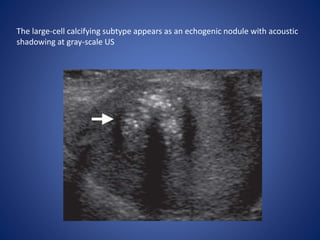

Sertoli Cell Tumors

The most common histologic variant in children and adolescents is the large-

cell calcifying subtype, which secretes testosterone and causes PPP in young

Imaging Features.—

At US, the appearance of Sertoli cell tumor is variable.

Sertoli cell tumor may also appear as multiple

homogeneous nodules with surrounding thin

The large-cell calcifying subtype appears as an echogenic nodule with acoustic

shadowing at gray-scale US

The large-cell calcifyingsubtype appears as an echogenic nodule with acoustic shadowing at gray-scale US